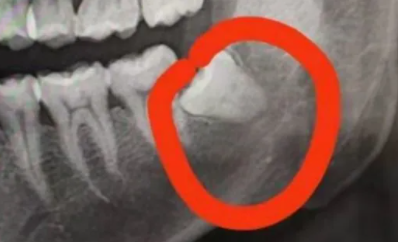

看图,年前在XX医院拔的,下颌完全没长出的,要2000元。由于智齿的牙根比较靠近牙神经,一般的医生都不敢拔,他们叫来了科室主任拔的。

拔之前签了一份协议书,大概就是说,由于智齿的牙根比较靠近神经,手术中可能会损坏牙神经,可能会导致下巴永久性麻木。口头说概率大概0.8%,概率不大,于是就签了。

手术打了麻醉针,还是有一点点痛的。先把牙肉隔开,然后把牙齿割开两半(旁边的牙齿顶到了,不割开是拿不出来的),拔完后缝针,整个过程用时1小时10分钟。

当然,我这科智齿算比较难拔的了,一般医生都不敢动手的那种。一般正常长出的智齿是不用缝针的,也不用那么贵。上颌大概4-5百一颗,下颌6-7百一颗。